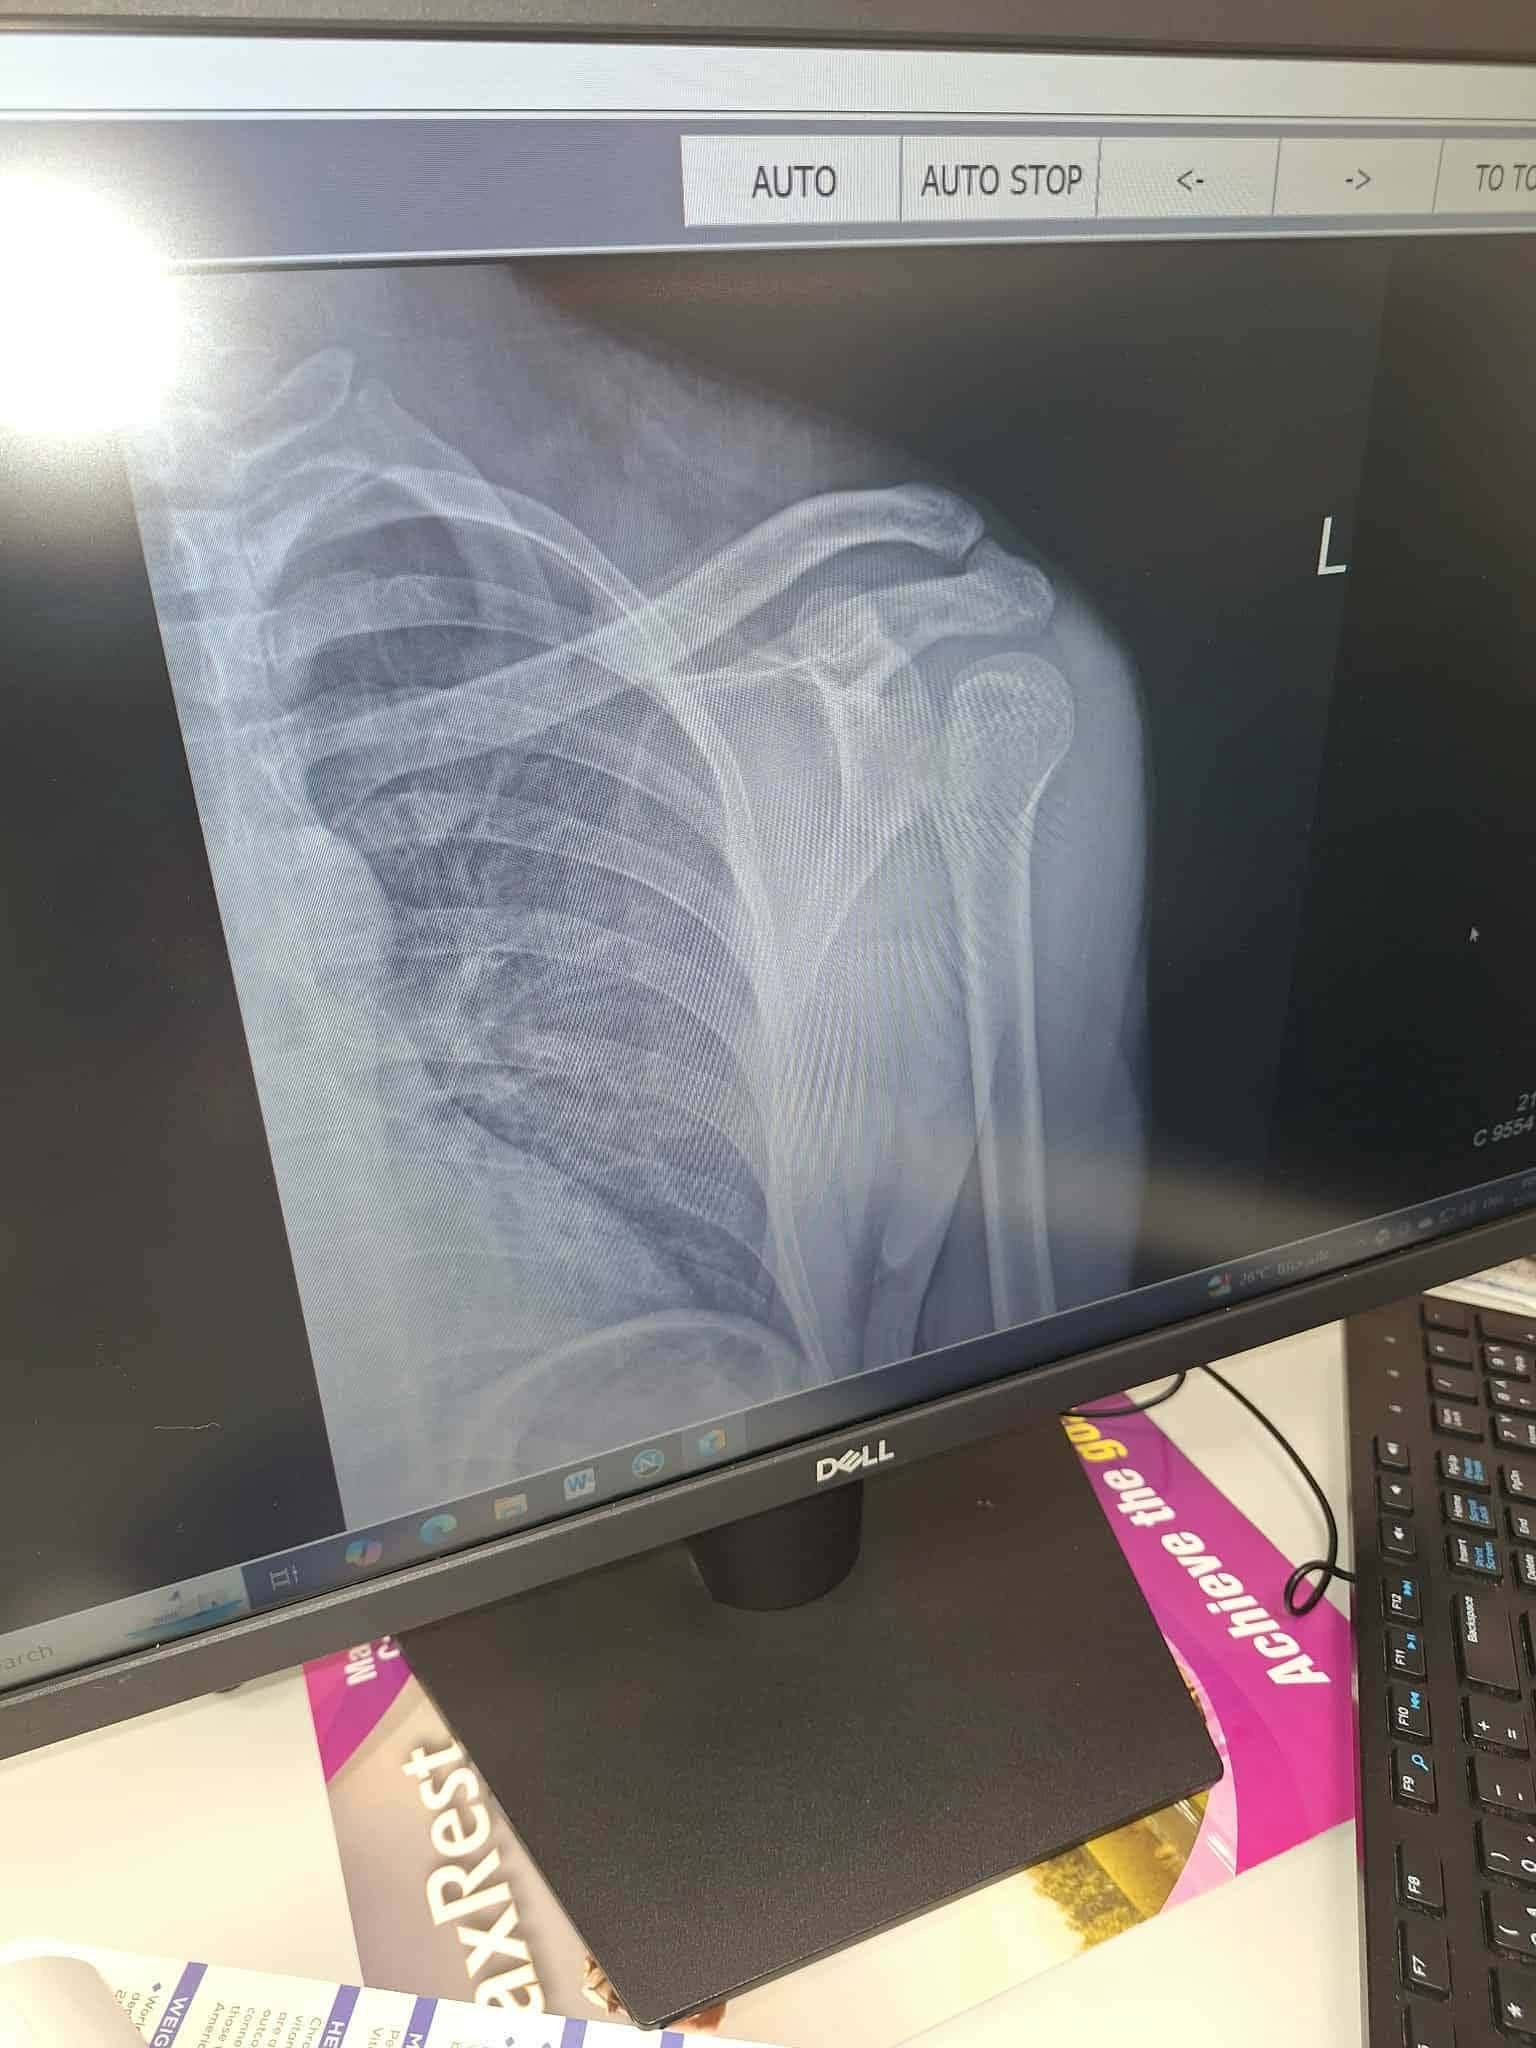

وفي تصريحات لـ"تليجراف مصر" قالت هبة السيد شقيقة أيمن، إنه سافر إلى المملكة منذ 4 سنوات بحثًا عن لقمة العيش، وكان يعمل في مجال السباكة والكهرباء، لكن قبل سنة ونصف تعرض لصعق كهربائي شديد، سقط على أثره من ارتفاع 3 طوابق، أدى إلى فصل ذراعه عن كتفه اليمنى، وفقدانه القدرة على تحريك أصابعه.

وأشارت هبه إلى أن شقيقها خضع لثلاثة عمليات جراحية فاشلة في السعودية، وخلال تلك الفترة طلب الكفيل من العائلة إرسال مبلغ مالي لتجديد عقد إقامة أيمن، لكنه اختلس الأموال وبدلًا من مساعدته تخلى عنه وكُتب له على خروج نهائي، دون أن يكون معه حق تذاكر العودة.